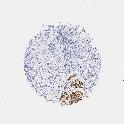

UROTHELIAL CANCER - Protein expressioni

A mouse-over function shows sample information and annotation data. Click on an image to view it in a full screen mode. Samples can be filtered based on level of antibody staining by selecting one or several of the following categories: high, medium, low and not detected. The assay and annotation is described here.

Note that samples used for immunohistochemistry by the Human Protein Atlas do not correspond to samples in the TCGA dataset.

Antibody stainingi

Antibody staining in the annotated cell types in the current human tissue is reported as not detected, low, medium, or high, based on conventional immunohistochemistry profiling in selected tissues. This score is based on the combination of the staining intensity and fraction of stained cells.

Each image is clickable and will lead to virtual microscopy that enables deeper exploration of all samples and also displays staining intensity scores, fraction scores and subcellular localization as well as patient and tissue information for each sample.

Antibody HPA008066

Antibody HPA017330

Antibody CAB000006

Staining

High

Medium

Low

Not detected

Intensity

Strong

Moderate

Weak

Negative

Quantity

>75%

75%-25%

<25%

None

Location

Nuclear

Cytoplasmic/membranous

Cytoplasmic/membranous,nuclear

Urothelial carcinoma, Low grade

Urothelial carcinoma, High grade